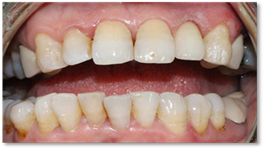

After the 3-month period required for osseointegration of the implant, the patient was seen for a digital impression for the definitive prosthesis and the fabrication of a Ti-base zirconia abutment (Figure 9), noting that the patient was under monthly clinical and radiological control. The crown was sealed, and the patient is satisfied with her crown both aesthetically and functionally (Figure 10).

Figure 10: Final result of implant rehabilitation.